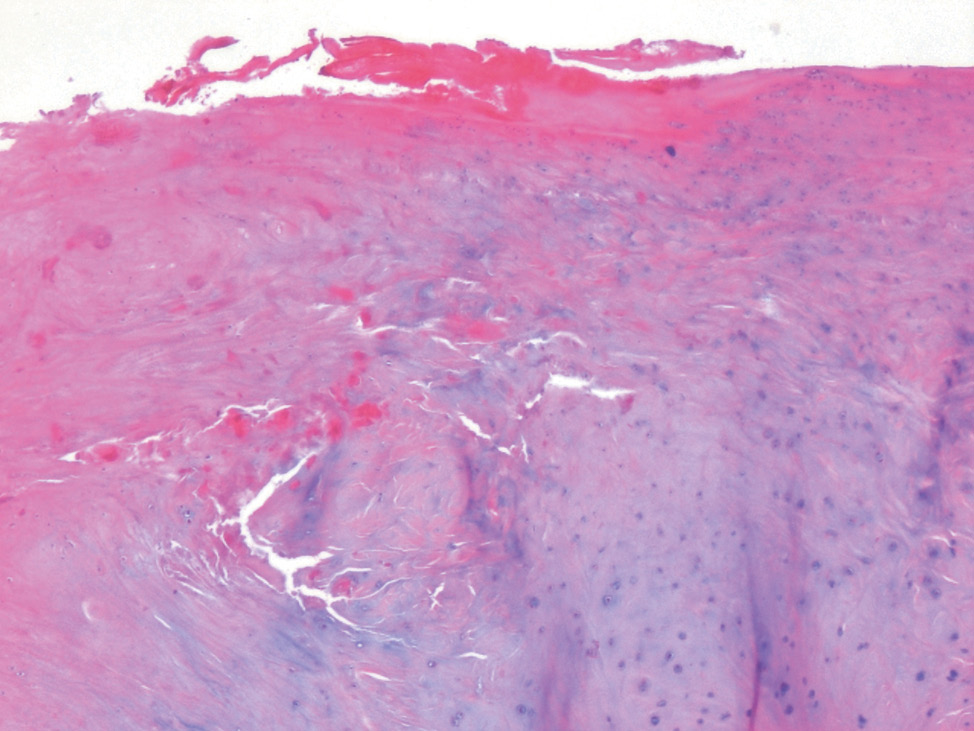

Костный мозг: преимущественно представлен жировой тканью с резким обеднением всех ростков кроветворения (рис. 2, 3).

Рис. 2. Костные балки, костный мозг. ×40, окраска гематоксилином и эозином. Костные балки утолщены, костный мозг преимущественно представлен жировой тканью с резким обеднением всех ростков кроветворения

Fig. 2. Bone rods, bone marrow. ×40, stained with hematoxilin and eosin. Bone rods are thickened. The bone marrow is mostly represented by adipose tissue with a substantial depletion of all the sprouts of hematopoiesis

Рис. 3. Костные балки, костный мозг. ×100, окраска гематоксилином и эозином. Костные балки утолщены, костный мозг преимущественно представлен жировой тканью с резким обеднением всех ростков кроветворения

Fig. 3. Bone rods, bone marrow. ×100, stained with hematoxilin and eosin. Bone rods are thickened. The bone marrow is mostly represented by adipose tissue with a substantial depletion of all the sprouts of hematopoiesis